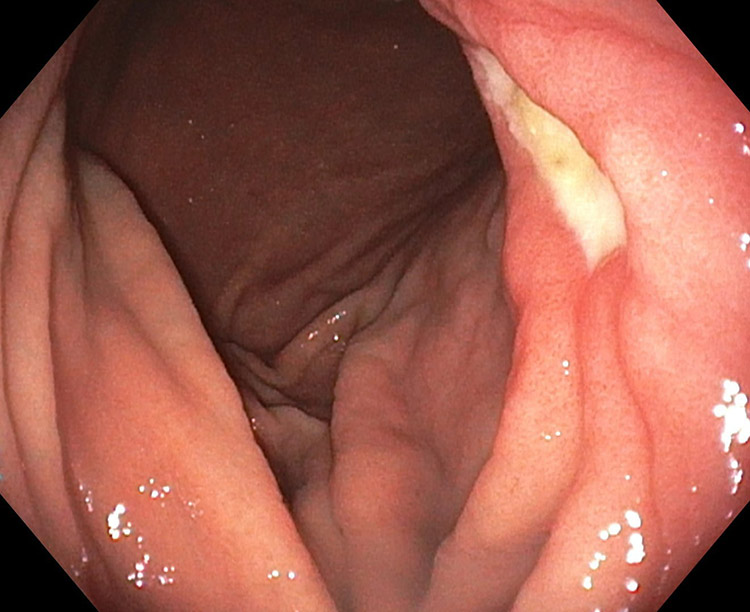

胃潰瘍

胃潰瘍・十二指腸潰瘍は、胃や十二指腸の粘膜が傷つき、えぐられたような「潰瘍(かいよう)」ができる病気です。多くはお薬で治療できますが、放置すると出血や穿孔(せんこう:穴があく)など重い合併症につながることがあるため、早めの受診が大切です。

検査と診断(胃カメラが重要です)

診断には胃カメラ(上部消化管内視鏡)が最も重要です。潰瘍の有無や場所、出血の程度を確認します。必要に応じて生検(組織検査)を行い、胃がんなど別の病気が隠れていないかも確認します。